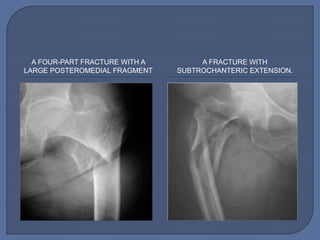

A FOUR-PART FRACTURE WITH A

LARGE POSTEROMEDIAL FRAGMENT

A FRACTURE WITH

SUBTROCHANTERIC EXTENSION.

A FOUR-PART FRACTUREWITH A LARGE POSTEROMEDIAL FRAGMENT A FRACTURE WITH SUBTROCHANTERIC EXTENSION.

• #32 The unstable patterns include reverse obliquity fractures, transtrochanteric fractures, fractures with a large posteromedial fragment implying loss of the calcar buttress, and fractures with subtrochanteric extension (Figs. 4 through 7)3-5,9,12-16.